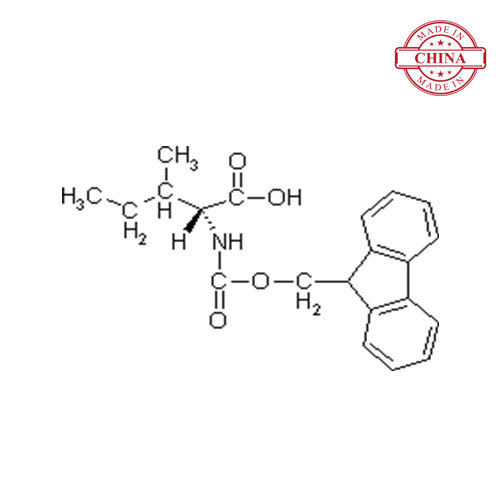

| रासायनिक नाम | Thymopentin |

| रासायनिक नाम | Thymopentin |